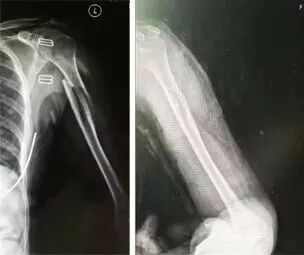

病例三

肱骨骨折

患者王某,女,62歲,因外傷導(dǎo)致左側(cè)肱骨骨折,患者來到嘉興邦爾骨科醫(yī)院富陽骨傷就診,當(dāng)即進行手法整復(fù)、固定以及外敷張氏金黃散。經(jīng)過每周換幫,1個月后骨折愈合,2個月功能恢復(fù)。

手法整復(fù)前后對比圖